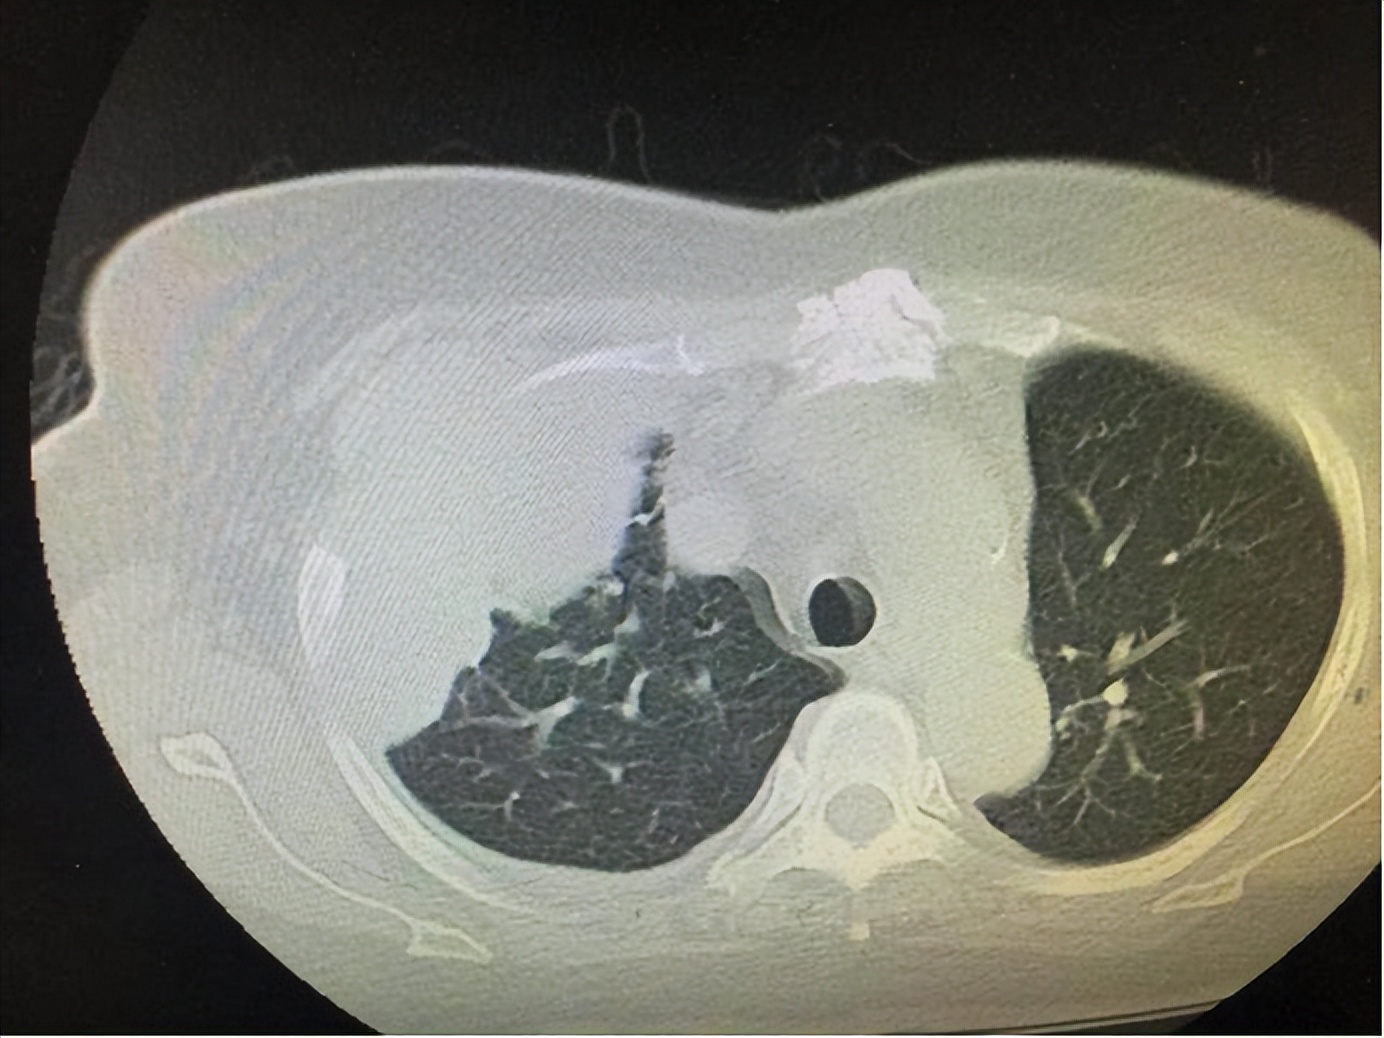

部分胸膜间皮瘤患者早期时可出现肩痛症状。间皮瘤是癌症的一种,多发于覆盖在内脏器官表面的薄层间皮组织,最为常见的被影响区域是腹部和胸壁的胸膜,在临床上被称为胸膜间皮瘤。

肺上沟癌也可引起患者的肩部疼痛。研究表明,肺上沟癌最常见的首发症状在于臂丛、壁胸膜、筋膜,第一、第二肋骨等部位受到癌细胞的侵犯可能会导致尖锐的后肩痛,同时患者的腋下或肩胛下区域也可能出现疼痛,并且疼痛还会向头部、颈部、胸部等部位扩散。